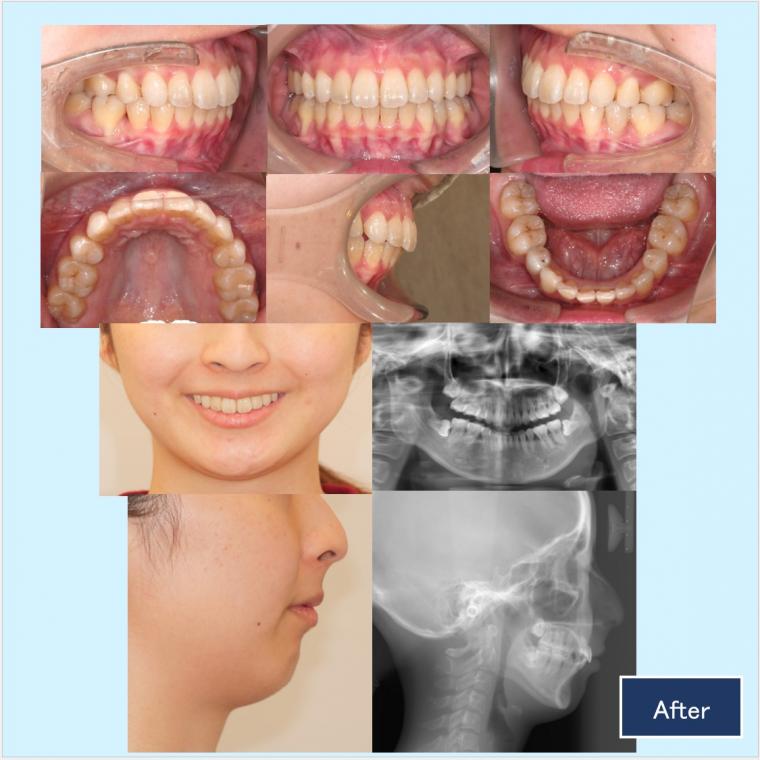

上顎両側4番、下顎両側5番を抜歯して、上下顎前歯部を後方移動致しました。

上顎臼歯部の頬側に歯科矯正用アンカースクリューを埋入して臼歯部の固定を行い、上顎前歯部を後方移動させていきました。また、ガミースマイルの改善のために上顎口蓋正中にも歯科矯正用アンカースクリューを植立させて、上顎前歯部に圧下力を加えました。

最終的な微調整では正中を出来る限り一致させる為に、顎間ゴムを使用して頂きました。

ご協力ありがとうございました。美しい口元、機能的な咬合をこれからもぜひ維持していきましょう。

治療に用いた主な装置:

◎歯科用アンカースクリュー

◎ハーフリンガル:上顎 カスタムメイド型リンガルブラケット矯正装置(インコグニート)下顎 セラミックラビアルブラケット矯正装置

抜歯部位:上顎両側4番、下顎両側5番

治療費:¥1.320.000-(通院費¥5.500別)

リスク・副作用:前歯の後方移動を行うと口元の突出感は確実に減少しますが、法令線が目立つなど好ましくない変化が起きることがあります。毎回の調整時にお顔全体の確認をして、前歯の引っ込め方の調整を行うことで、好ましくない変化を予防して理想的な仕上がりを目指しています。